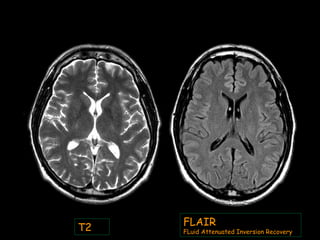

T1 T2

T2

FLAIR

FLuid Attenuated Inversion Recovery